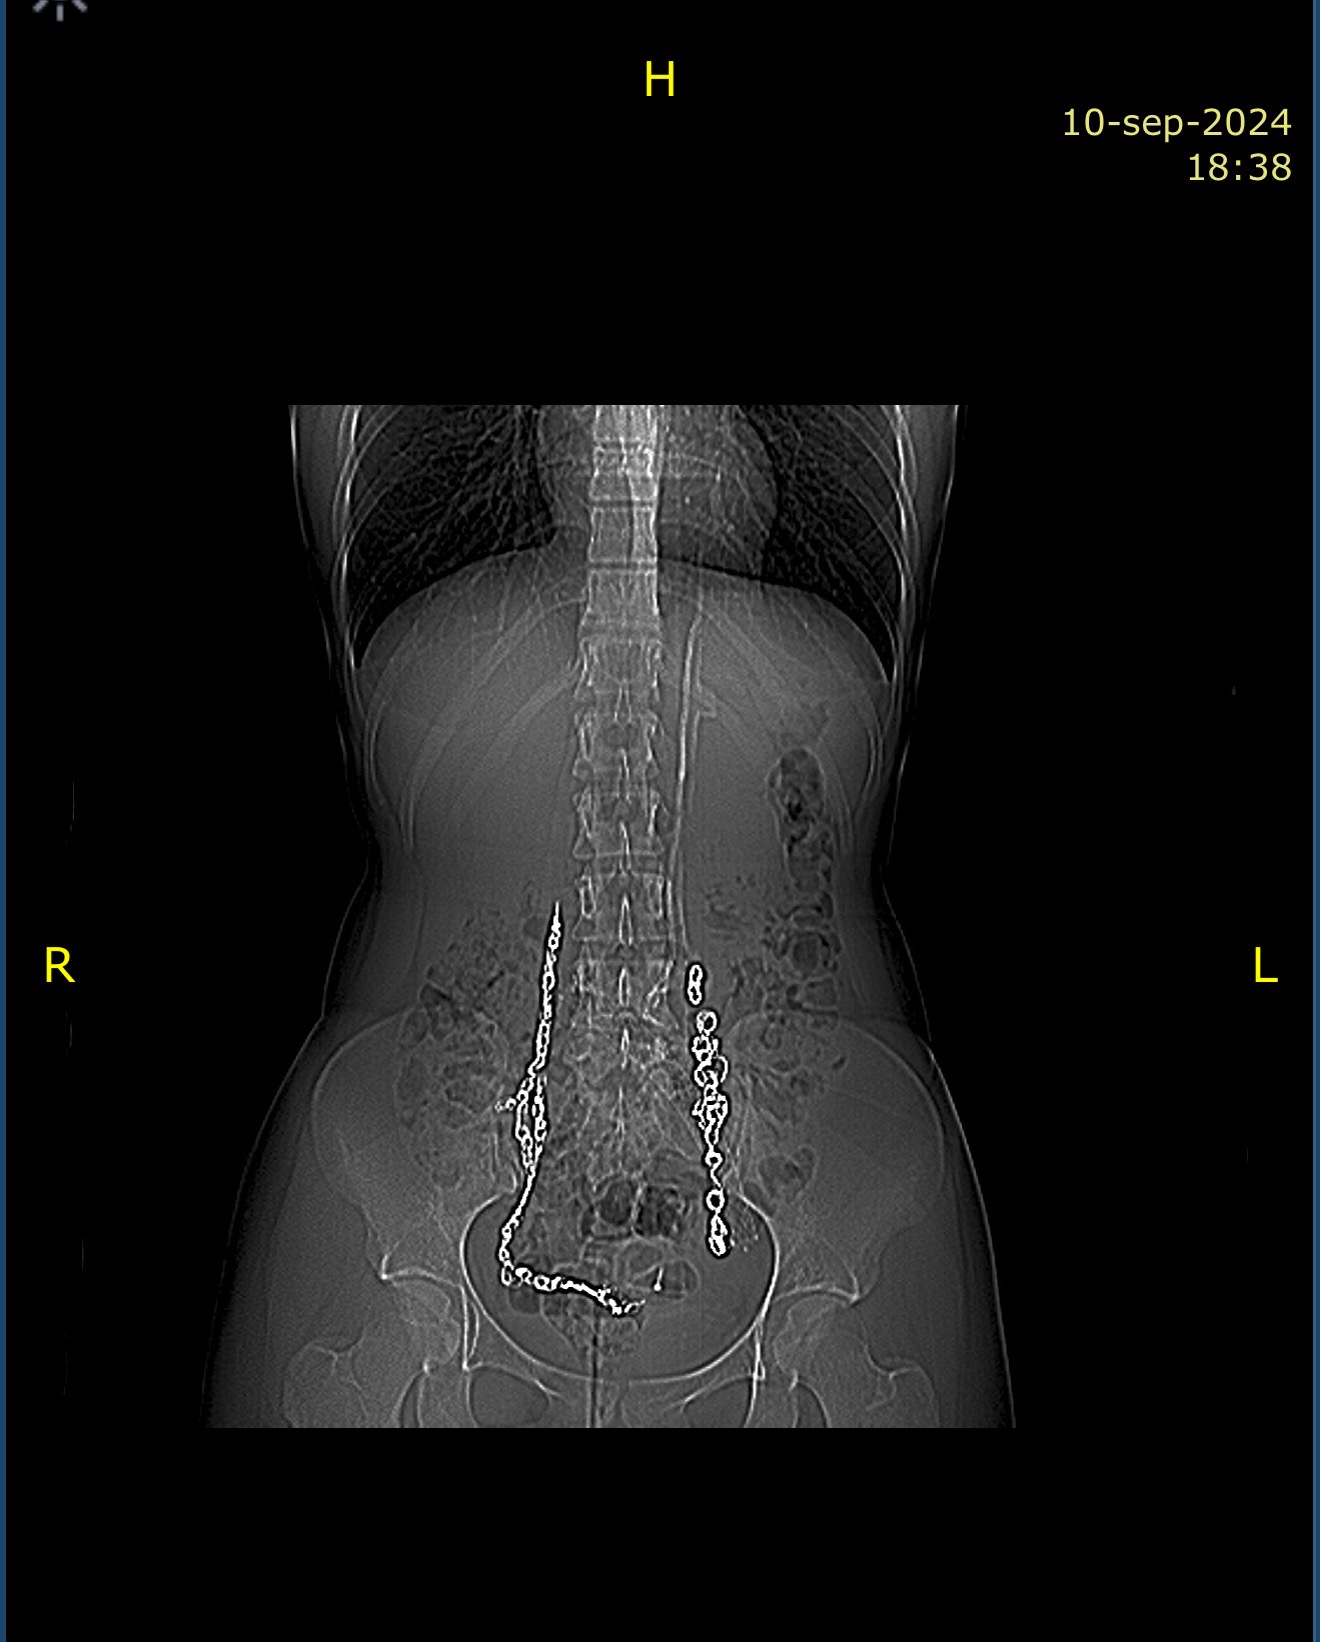

Estoy diagnosticada con un cuadro clínico complejo y raro que combina:

• Síndromes Vasculares Compresivos: (Cascanueces, May-Thurner, Congestión Pélvica) que me causan un dolor insoportable.

• Neuropatías y Radiculopatías: Daño nervioso que afecta mis piernas y zona pélvica, limitando mi movilidad.

• Condiciones Crónicas: Endometriosis profunda, Adenomiosis y Síndrome de Ehlers-Danlos, que agravan todo mi cuadro.

He pasado por múltiples intervenciones que, lejos de mejorarme, han complicado mi estado. He perdido mi trabajo y mi independencia.

I have been diagnosed with a complex and rare clinical profile that combines:

• Vascular Compressive Syndromes: (Nutcracker, May-Thurner, Pelvic Congestion) that cause unbearable pain.

• Neuropathies and Radiculopathies: Nerve damage affecting my legs and pelvic area, severely limiting my mobility.

• Chronic Conditions: Deep Endometriosis, Adenomyosis, and Ehlers-Danlos Syndrome, which aggravate my entire condition.

I have undergone multiple procedures that, rather than improving my state, have only complicated it. I have lost my job and my independence.